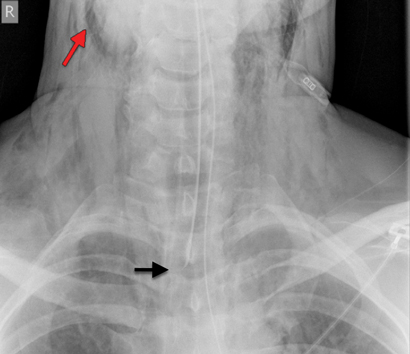

Mechanical ventilation was carried out initially with a portable unit (Weinmann Medumat Standard-a), on minute volume cycle with a minimum available pressure of 20 cm H2O. Subsequent chest x-ray showed extensive surgical emphysema (Figure) and air mediastinum, at which point he was moved to the operating theatre to allow lower pressure ventilation using an anaesthetic ventilator. The ETT was shifted further down the trachea to tamponade the site of traumatic injury, and reduce bleeding and tissue emphysema.